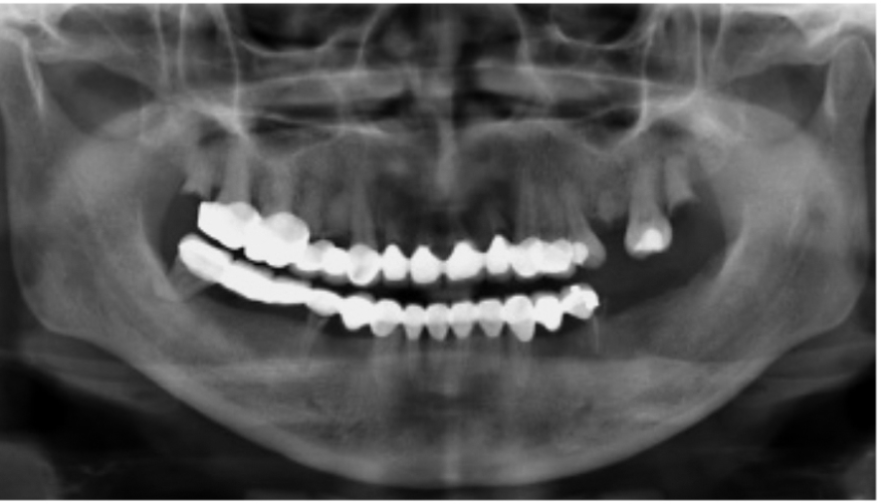

图3 术前全景片

图4 同一患者术后全景片